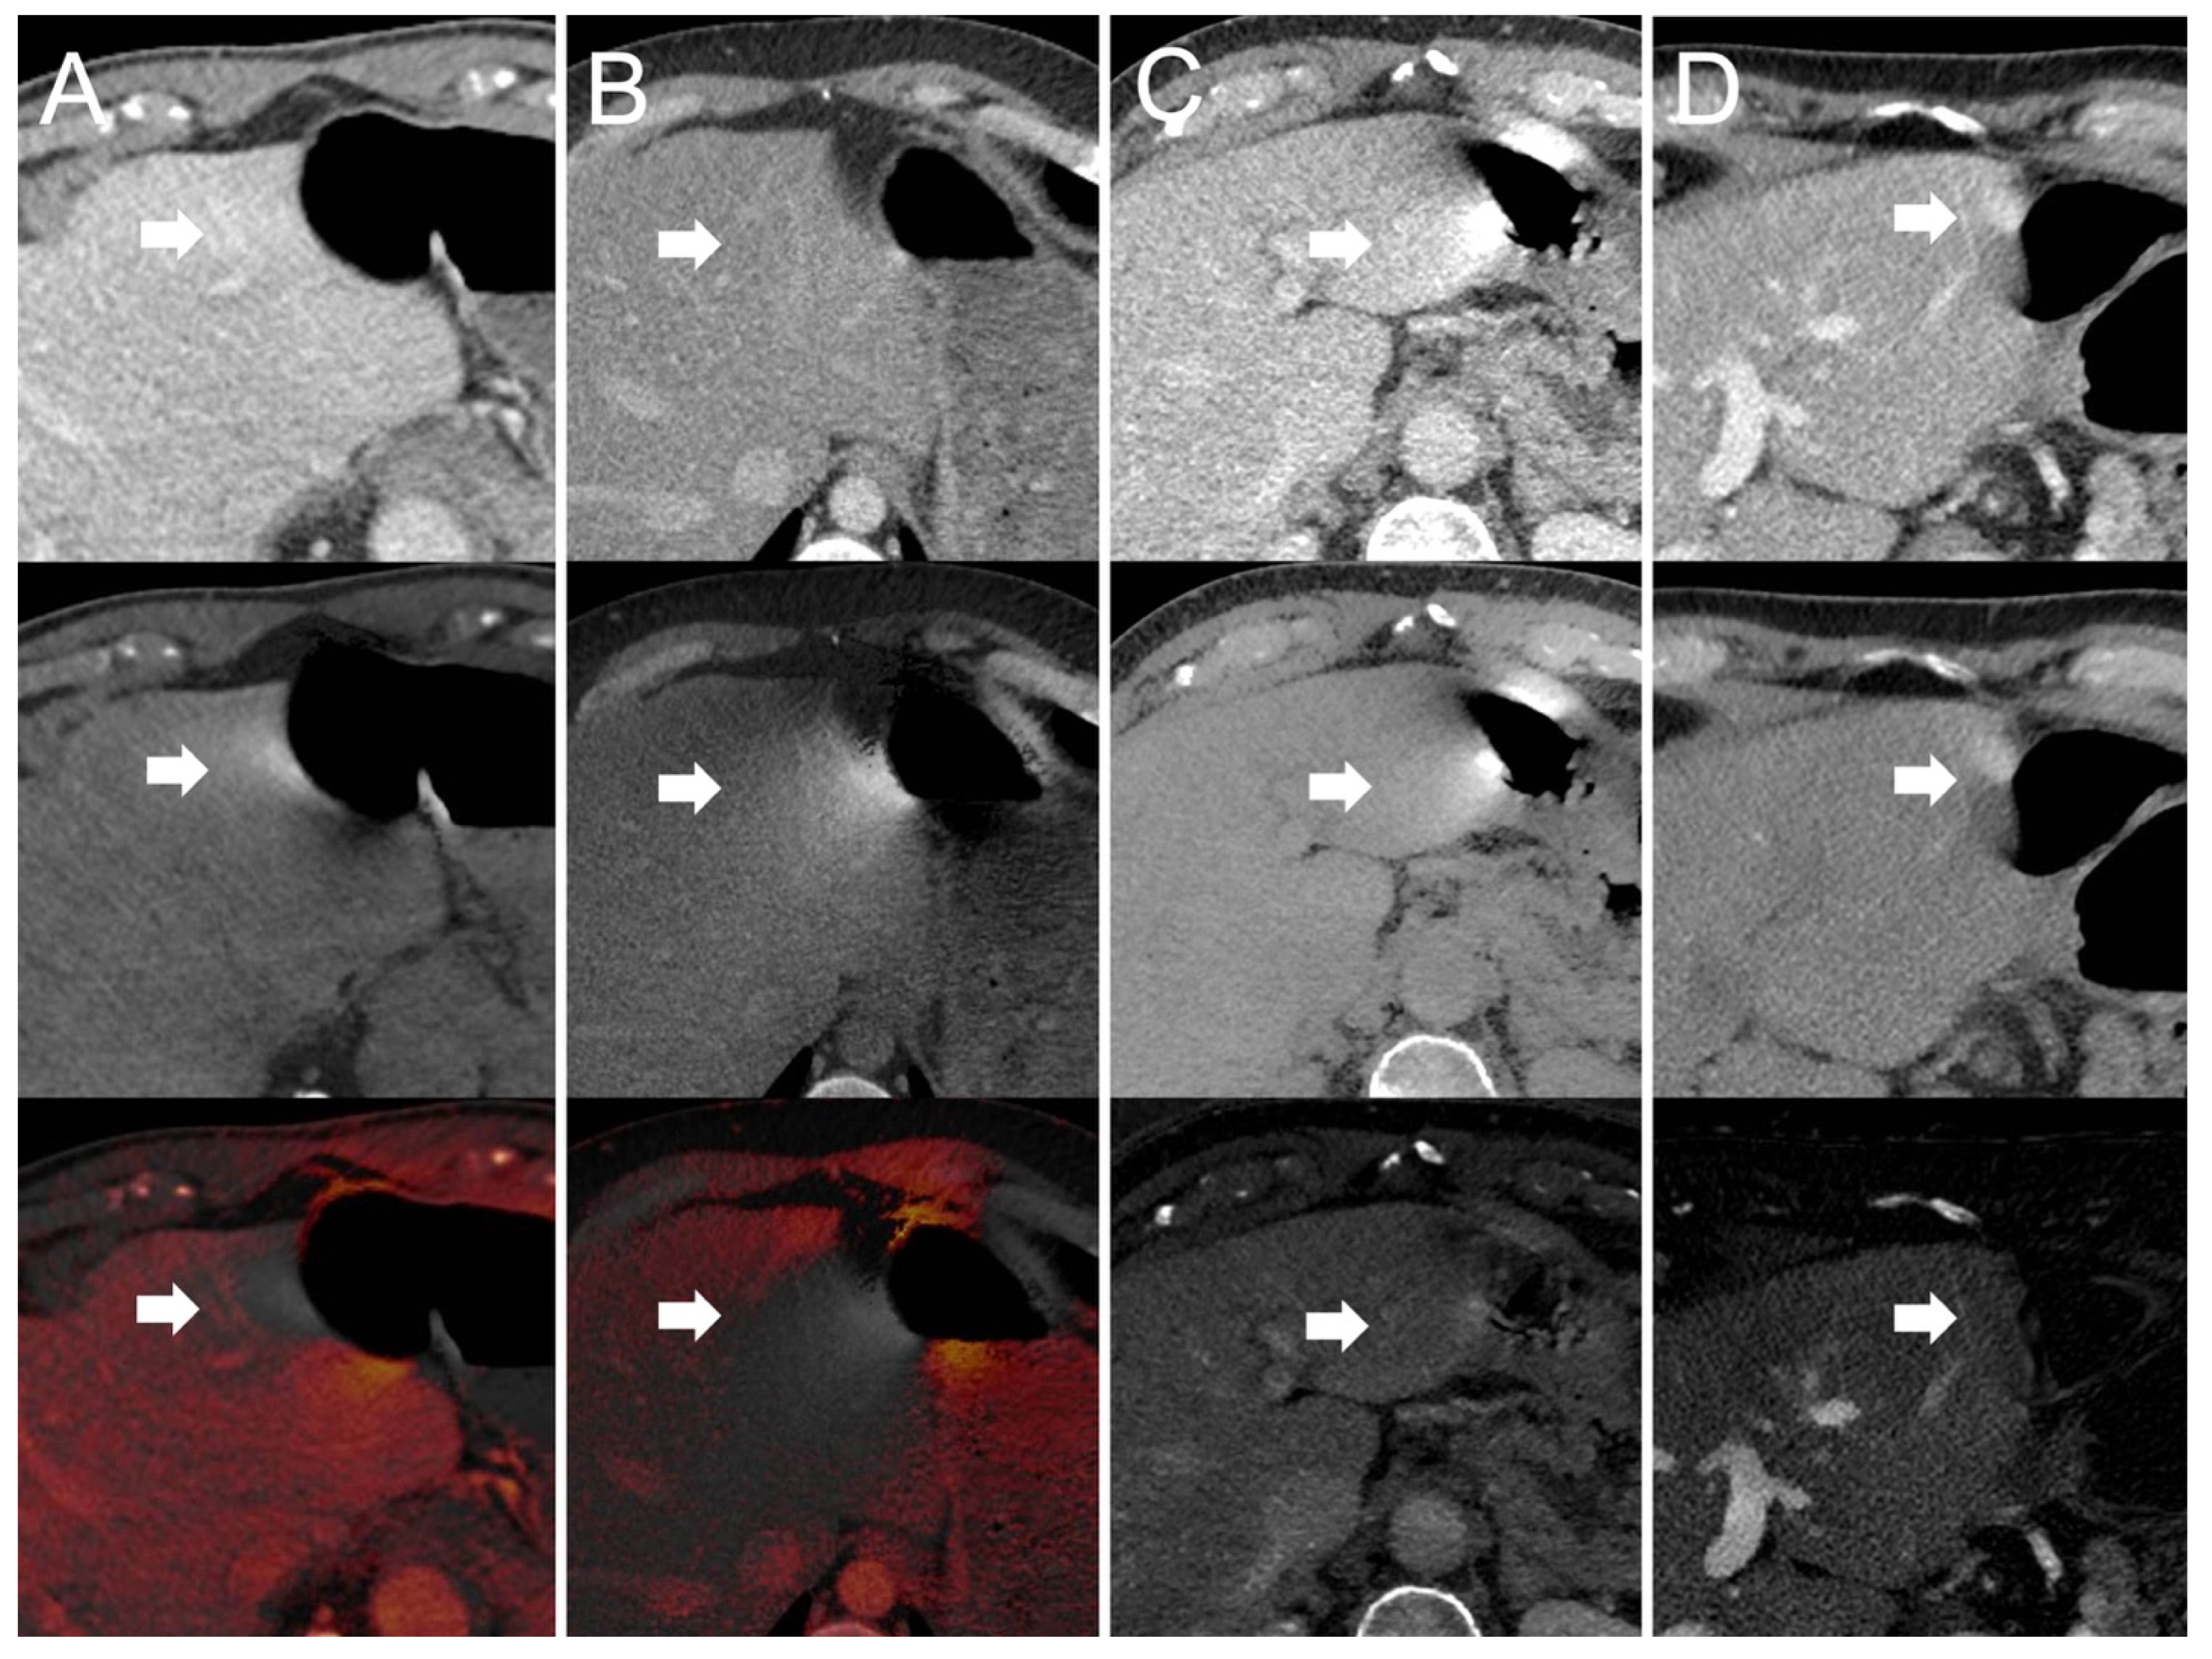

- Dual-source scanner: Depth of extension of visceral-motion-related artifacts into the liver (see Figure 2 and Figure 3) was significantly shorter (p < 0.001, each) for 120-kVp-like images (mean length: 5 ± 6 mm) compared with 40-keV (mean length: 16 ± 11 mm), 190-keV (mean length: 16 ± 9 mm), VNC (mean length: 15 ± 10 mm), and iodine (mean length: 16 ± 11 mm) images. Mean ROI measurements (HU or iodine concentration, respectively) were significantly different in the bright and dark artifact components compared to the neighboring liver parenchyma not affected by artifacts in 40-keV (p < 0.001, each), 190-keV (p < 0.001, each), VNC (p < 0.001, each), and iodine images (p < 0.001, each). However, in 120-kVp-like images, mean ROI measurements were not significantly different in bright (ROImin) artifact components compared to unaffected liver parenchyma (p = 0.32), as opposed to dark (ROImax) artifact components (p < 0.001).

- Twin-beam scanner: Depth of extension of visceral-motion-related artifacts into the liver was significantly shorter (p < 0.001, each) for 120-kVp-like images (mean length: 4 ± 5 mm) compared with 40-keV (mean length: 18 ± 12 mm), 190-keV (mean length: 16 ± 11 mm), VNC (mean length: 15 ± 11 mm), and iodine (mean length: 16 ± 11 mm) images. Mean ROI measurements were significantly different in the bright and dark artifact components compared to unaffected liver parenchyma in 120-kVp-like (p = 0.006, p = 0.03), 40-keV (p < 0.001, each), 190-keV (p < 0.001, each), VNC (p < 0.001, each), and iodine images (p < 0.001, each).

- Fast kV-switching scanner: Depth of extension of visceral-motion-related artifacts into the liver was significantly shorter (p < 0.001, each) for iodine (mean length: 6 ± 7 mm) images compared with 120-kVp-like (mean length: 11 ± 7 mm), 40-keV (mean length: 9 ± 8 mm), 140-keV (mean length: 10 ± 8 mm), and VNC (mean length: 13 ± 8 mm) images. Mean ROI measurements were significantly different in the bright and dark artifact components compared to unaffected liver parenchyma in 120-kVp-like (p < 0.001, each), 40-keV (p < 0.001, each), 140-keV (p < 0.001, each), VNC (p < 0.001, each), and iodine images (p < 0.001, each).

- Dual-layer spectral detector scanner: Depth of extension of visceral-motion-related artifacts into the liver was significantly shorter (p < 0.001, each) for iodine (mean length: 2 ± 5 mm) images compared with 120-kVp (mean length: 11 ± 5 mm), 40-keV (mean length: 10 ± 6 mm), 200-keV (mean length: 11 ± 5 mm), and VNC (mean length: 11 ± 5 mm) images. Mean ROI measurements were significantly different in the bright and dark artifact components compared to unaffected liver parenchyma in 120-kVp (p < 0.001, each), 40-keV (p < 0.001, each), 200-keV (p < 0.001, each), and VNC (p < 0.001, each) images. However, in iodine images mean ROI measurements were not significantly different in bright (ROImax) artifact components compared to unaffected liver parenchyma (p = 0.15), as opposed to dark (ROImin) artifact components (p < 0.001). Further details on quantitative artifact measurements are provided in Table 2 and the Supplementary Material.

- Dual-source scanner: Qualitative artifact scores (see Figure 4) were significantly lower (p < 0.001, each) for 120-kVp-like images (median score: 2, range: 1–5) compared with 40-keV (median score: 4, range: 1–5), 190-keV (median score: 3, range: 2–5), VNC (median score: 3, range: 2–5), and iodine (median score: 4, range: 1–5) images.

- Twin-bean scanner: Qualitative artifact scores were significantly lower (p < 0.001, each) for 120-kVp-like images (median score: 2, range: 1–4) compared with 40-keV (median score: 5, range: 1–5), 190-keV (median score: 3, range: 2–5), VNC (median score: 3, range: 1–5), and iodine (median score: 4, range: 1–5) images.

- Fast kV-switching scanner: Qualitative artifact scores were significantly lower (p < 0.001, each) for iodine images (median score: 2, range: 1–5) compared with 120-kVp-like (median score: 3, range: 1–5), 40-keV (median score: 3, range: 1–5), 140-keV (median score: 3, range: 1–5), and VNC (median score: 3, range: 1–5) images.

- Dual-layer spectral detector scanner: Qualitative artifact scores were significantly lower (p < 0.001, each) for iodine images (median score: 1, range: 1–3) compared with 120-kVp (median score: 3, range: 1–5), 40-keV (median score: 3, range: 1–5), 200-keV (median score: 3, range: 2–5), and VNC (median score: 3, range: 1–5) images. Further details on qualitative artifact scores are provided in the Supplementary Material.